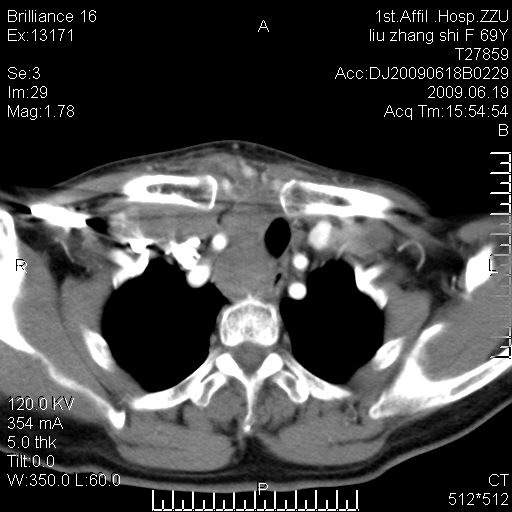

标题: CT26782:女,69岁,颈部占位,3天后公布病理结果。

【病理证实系列】女,69岁,颈部占位,有病理结果,3天后公布。(由于病例时间较久,临床资料不全,请网友见谅)本系列将有几百种常见、少见及罕见病例,均经病理证实。病例资料来自郑州大学第一附属医院。与网友共享,本人有空就发。

甲状腺癌并颈部淋巴结转移。感谢楼主的良苦用心,谢谢。

甲状腺癌并颈部淋巴结转移。

需与鼻咽癌鉴别!

支持甲状腺癌广泛侵及周围结构并颈部淋巴结转移。

鉴别:淋巴瘤、恶性神经源性病变、恶性纤维组织细胞瘤。

病理结果:颈部非霍奇金淋巴瘤。